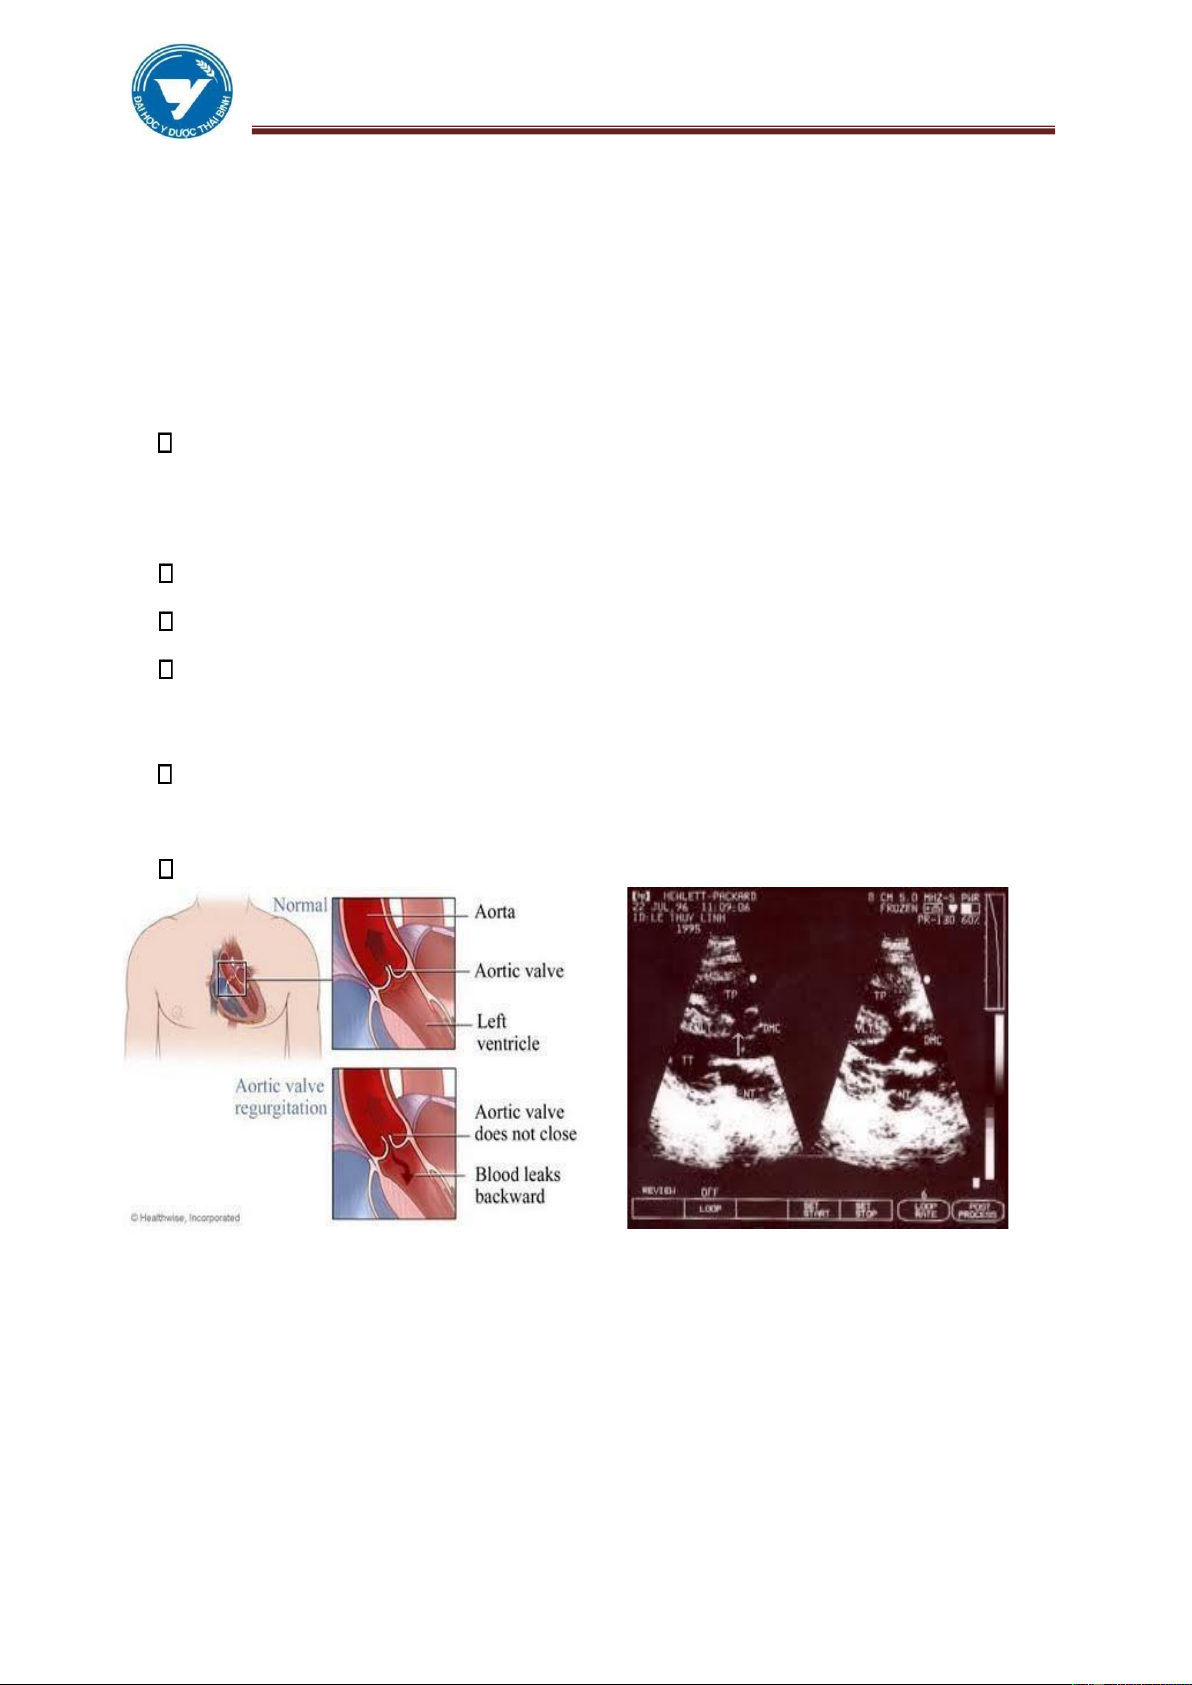

4.1. Hở van ộng mạch chủ

Nguyên nhân thường gặp nhất là sau thấp tim. Các nguyên nhân khác bao

gồm: Giang mai, Viêm nội tâm mạc nhiễm khuẩn, Hội chứng Marfan, Chấn

thương, ĐMC bóc tách, Viêm khớp dạng thấp.

Sinh lý bệnh: Máu phụt ngược vào thất trái trong kỳ tâm trương, tăng thể

tích, lưu lượng gây giãn buồng thất trái. Giãn vòng van 2 lá, hở van 2 lá cơ năng giãn buồng nhĩ trái.

Thất trái giãn hình tròn mõm tim dưới cơ hoành trên phim thẳng,

trên phim nghiêng trái và chếch trước phải thấy chèn ép một phần ba dưới thực quản. Chỉ số T/N > 0,6.

ĐMP không to, có khi như lõm vào.

ĐMC lên thường không giãn, nếu ĐMC lên giãn rõ,phải coi chừng có

kết hợp với Hẹp van ĐMC. Quai ĐMC hầu như không thay ổi.

Siêu âm: Dấu hiệu gián tiếp áng tin hơn là trực tiếp. Rung tâm trương

của van hai lá giãn thất trái mà không dày thành , tăng ộng thất trái.

Hình 3.17. Hở van ĐMC